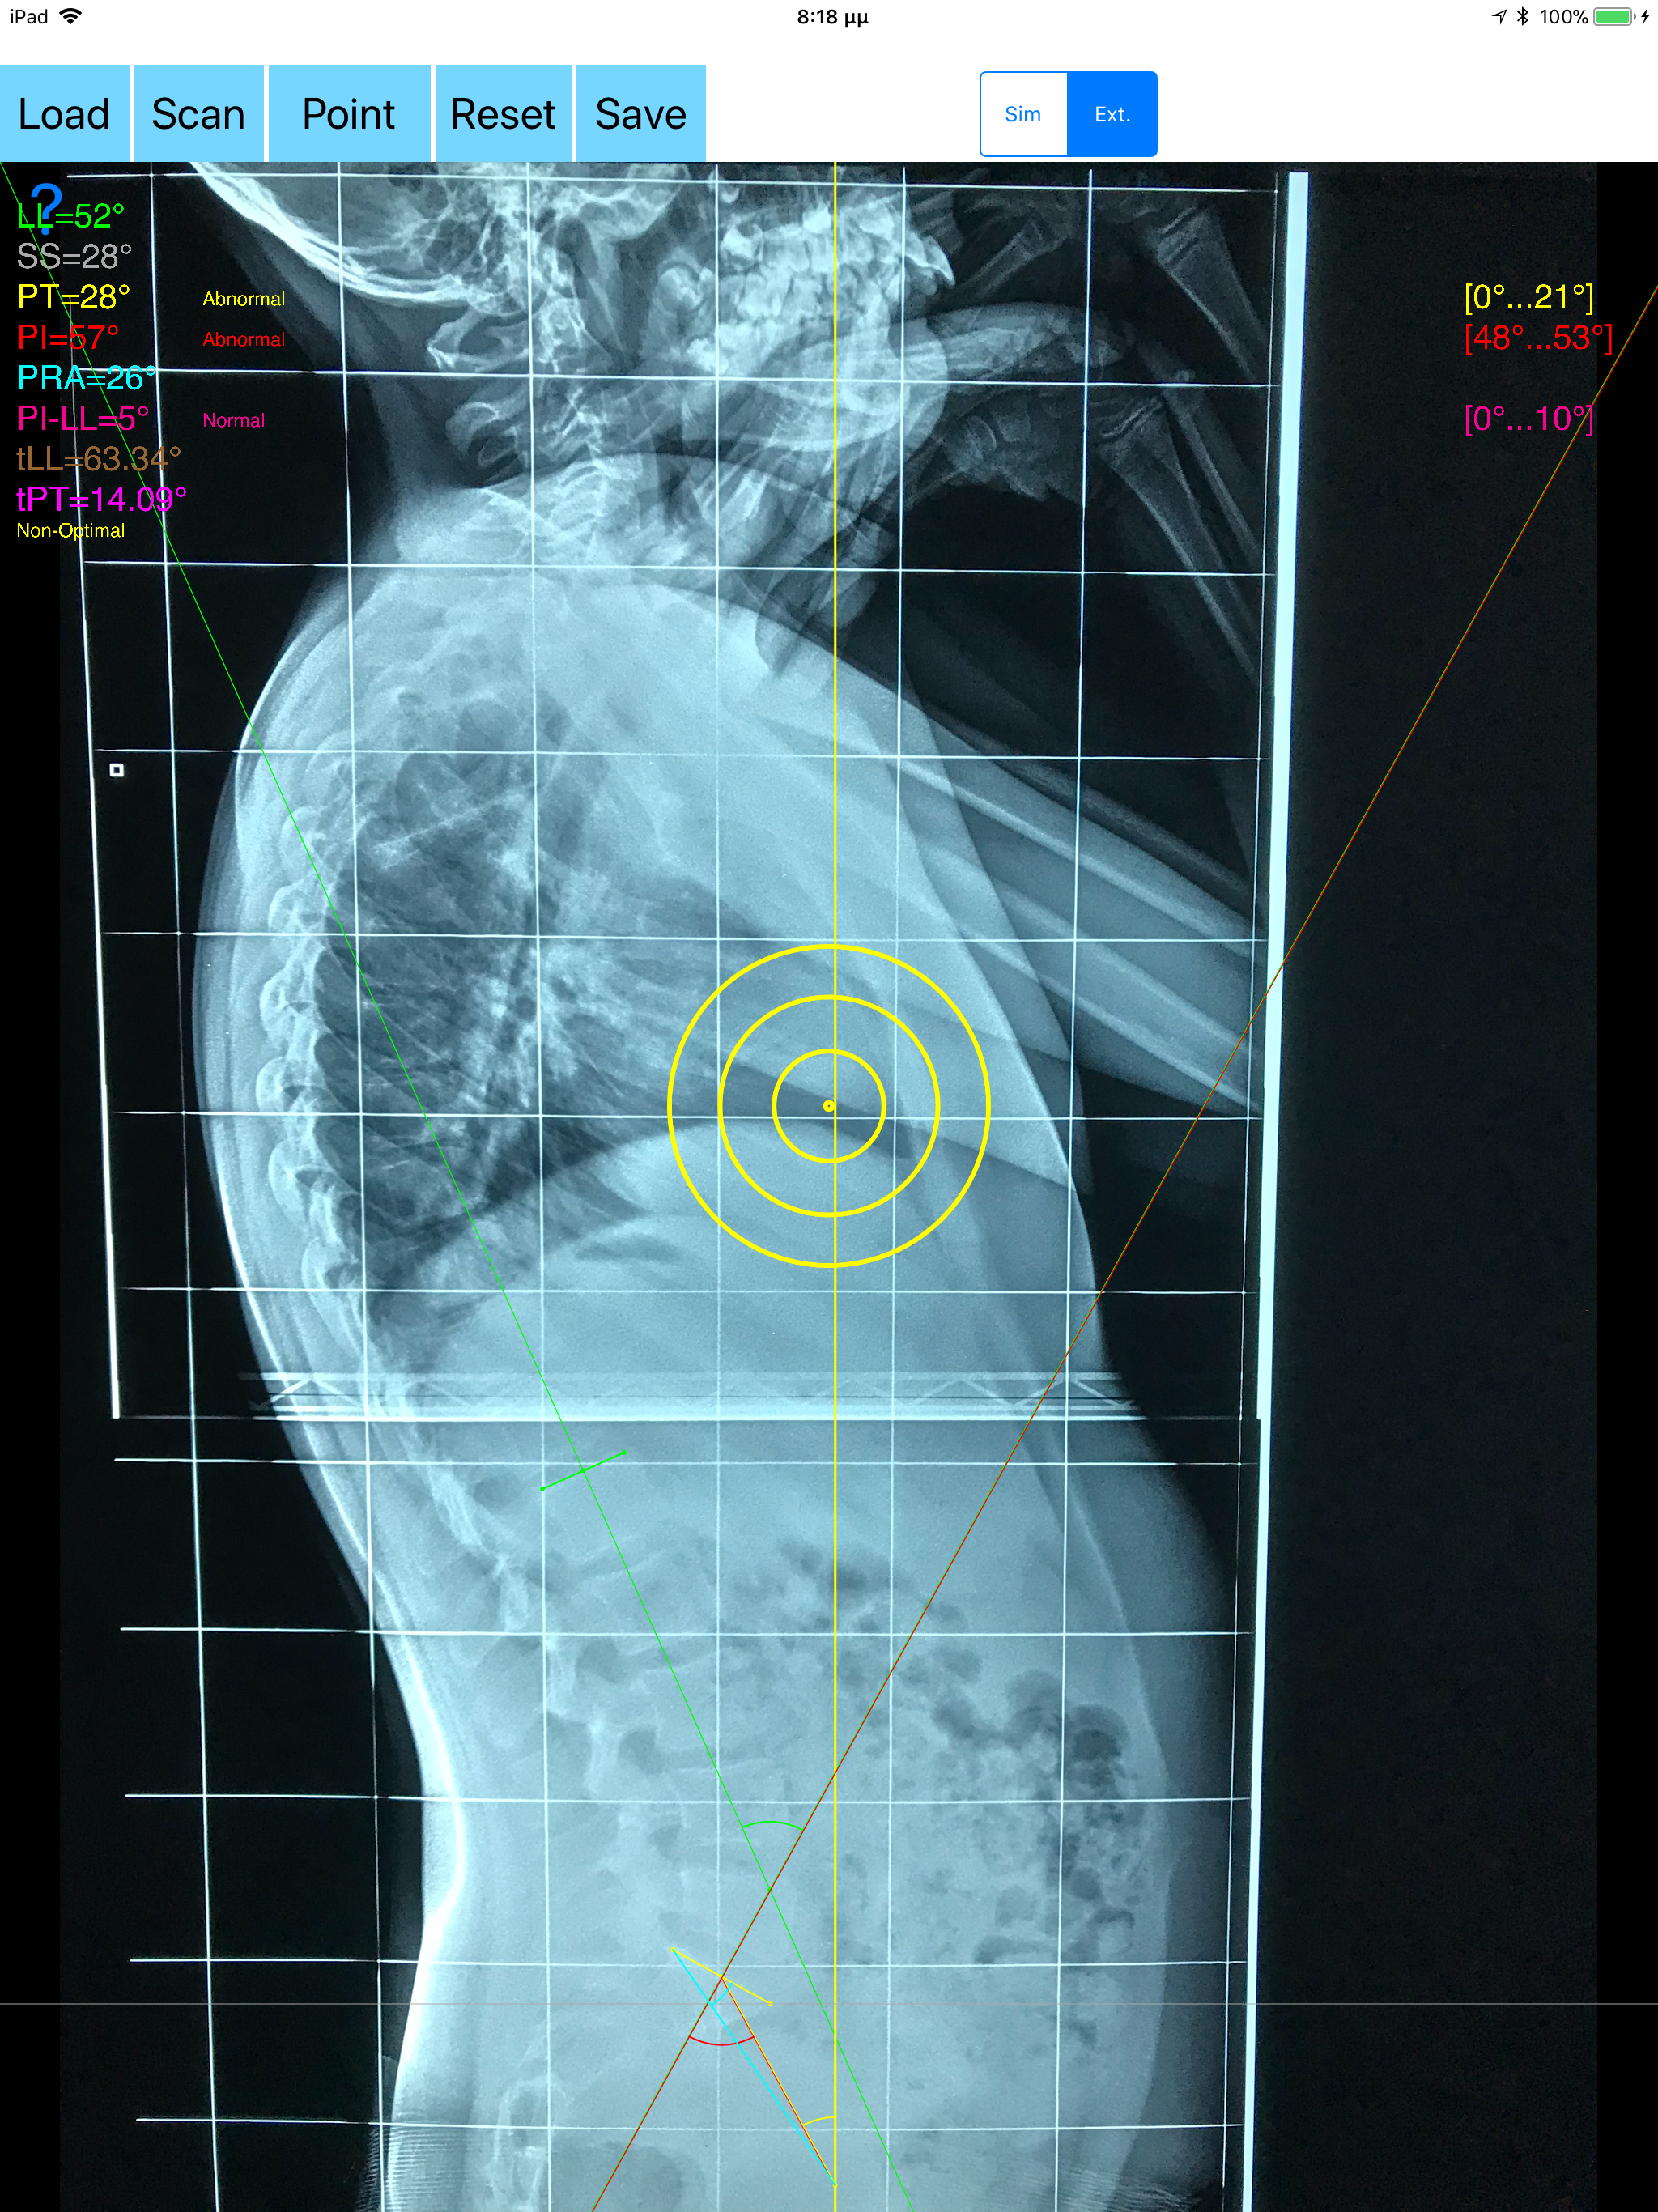

The assessment of the parameters involved in spinopelvic jucture are of paramount importance for spine and joint replacement surgeon. The dynamic interplay between flexibility and balance around the axis of gravity determine the type and the amount of influence in spine and hips. Radiographic parameters to evaluate objectively the spinopelvic sagittal balance are Pelvic incidence (PI), Sacral slope (SS), Pelvic Tilt (PT), Lumbar lordosis (LL). Drawings in patients X-rays and precise measurements are important in order to quantify the magnitude of spinal deformities, to monitor the success or failure of treatment and thus optimise the management of patients according to the severity of the imbalance or even to identify patient at risk of degenerative spondylolisthesis or disk herniation. The Spinopelvic Balance App is medical software aimed for orthopaedic surgeons, providing tools that allow doctors to: -Securely import medical images directly from the camera or stored photos. -By marking few points at the image of X-ray, the App calculates and offers a very convenient way to determine the most accurate possibly way at once, Pelvic incidence (PI), Sacral slope (SS), Pelvic Tilt (PT), Lumbar lordosis (LL), thoracic kyphosis, PI–LL Pelvic incidence Angle (PI) minus Lumbar lordosis Angle (LL) PI–LL, theoretical normal pelvic tilt (tPT),theoretical normal L1-S1 lumbar lordosis (tL1S1), Pelvic Radius Angle (PRA). According to measured parameters the app categorises the severity of the imbalance of spine, in different stages: optimal or non optimal. -Save the planned images, for later review or consultation.The measured values are compared by normal reference databases and also data are exported as txt file, ready to print or to input as cells to excel for research. -The app allows choosing between simple and extended method according to everyday preference and also by choosing points in vertebra body in a independent manner from order. -The app can be used to measure L5 Incidence (L5I) Angle or L4 respectively. -The app offers theoretical value estimation this is particularly useful because a sensible difference between theoretical value and measured value reveals a compensation phenomenon if the pelvis tilt (PT) is higher than its theoretical value, then it is due to pelvis retroversion, which is a compensation phenomenon. Knowing the theoretical value of Pelvis Tilt (PT) provided it is easy to understand that a sensible difference between theoretical value and measured value is a compensation phenomenon. All information received from the software output must be clinically reviewed regarding its plausibility before patient treatment! Spinopelvic Balance App indicated for assisting healthcare professionals. Clinical judgment and experience are required to properly use the software.The software is not for primary image interpretation. In a busy everyday practice, the examiner have to draw lines in X-rays or in clinical settings, this it is time consuming and cumbersome. Accessory instruments like protractors, hinged goniometers, well sharped pencils, rulers or even transparent papers must be available. The app offers a very convenient and accurate way to perform most common radiographic measurements for spine, at the spinopelvic juncture in a blink of an eye in front of your screen. The build in feature of the app, allows results to be categorized may help decide what could be considered normal or pathologic. The app is not a simple goniometer, is an enhanced product which helps to monitor objectively the course of the treatment and evaluate optimally the spine. This App is particular useful in clinical settings where you need a quick results without losing time.Please see tutorial videos at the developer’s web Reference 1.Nunes VR, et al.Spinopelvic balance evaluation of patients with degenerative spondylolisthesis L4L5 and L4L5 herniated disc who underwent surgery.Rev Bras Ortop. 2016 Sep 22;51(6):662-666.